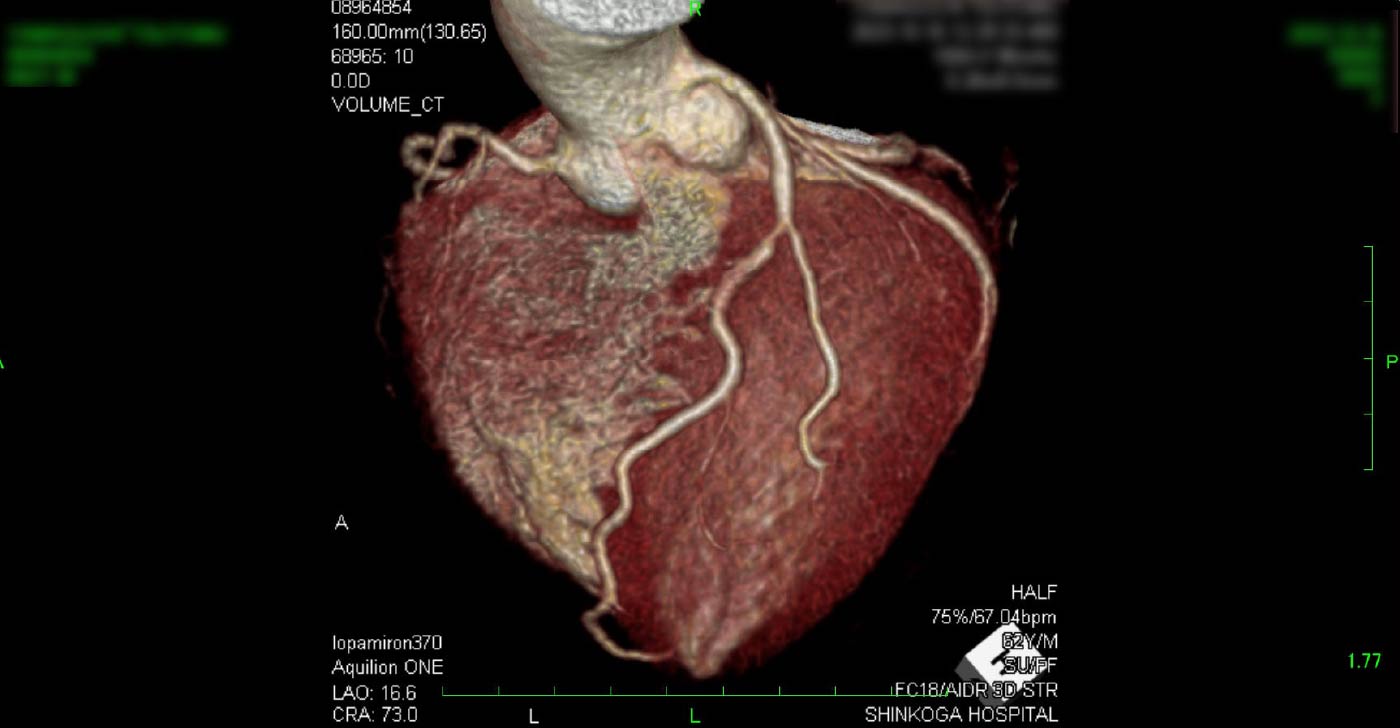

進行期 造影心臓CT 重症心筋虚血症例

冠動脈CT

狭心症を安全に診断あるいは除外する!

連携施設の新古賀病院で速やかに実行可能です。

冠動脈CT 冠動脈CT 冠動脈CT 冠動脈CT 冠動脈CT 冠動脈CT 冠動脈CT 冠動脈CT 冠動脈CT 冠動脈CT 冠動脈CT 冠動脈CT 冠動脈CT 冠動脈CT